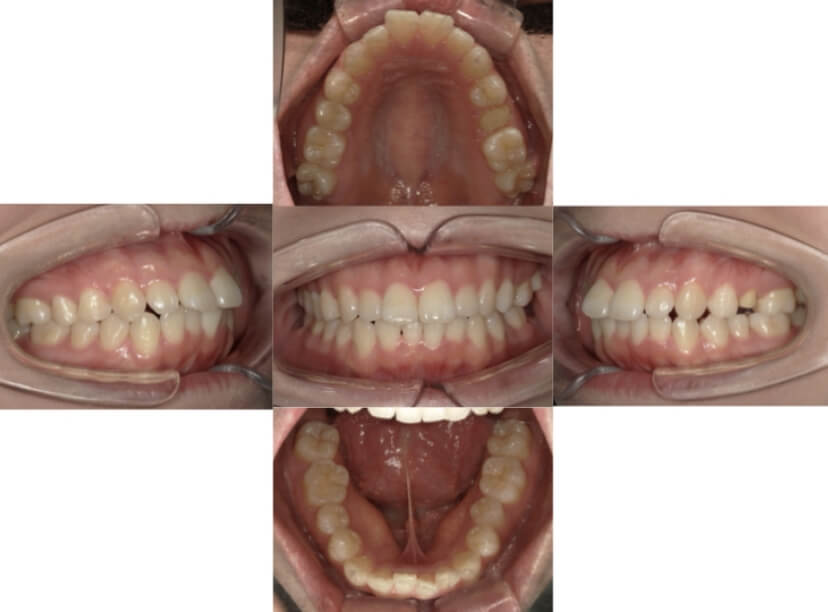

症例10

叢生

抜歯

ブラケット矯正

症例解説

上下顎叢生(上下の前歯のガタガタ)のケースです。

装置はラビアル(上下表側)で、上下顎の小臼歯を4本抜歯を行っています。抜歯したスペースを利用し、上下の前歯の後方移動と叢生(ガタガタ)の改善を行っています。口元の出っ張りを改善するため、歯科用アンカースクリューを使用して前歯の後方移動を行いました。

主訴 上下の前歯のガタガタを治したい。 口元を引っ込ませたい。

年齢・性別 22歳 女性

お住まいの地域 東京都大田区

治療方針 抜歯スペースを利用して上下前歯の叢生(ガタガタ)の改善

抜歯部位 上下顎左右第一小臼歯

使用装置 ラビアル(上下表側)、顎間ゴム、歯科用アンカースクリュー

治療期間 2年1か月

治療回数 20回

リテーナー クリアリテーナー

BEFORE

AFTER